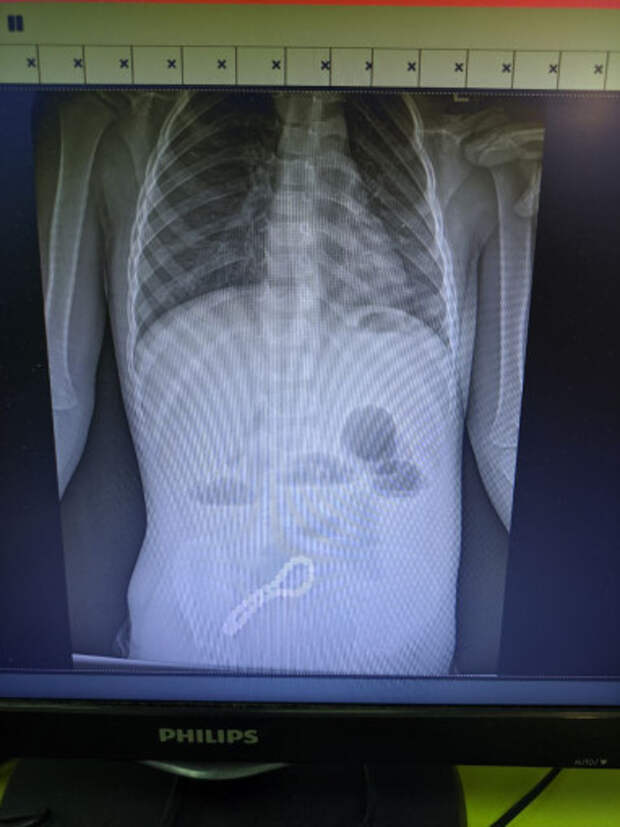

Ребенок попал в больницу с жалобами на проблемы с пищеварением. Медики предположили наличие в ЖКТ инородного тела, что подтвердил рентген.

"Было принято решение об операции. Мы провели минилапаротомию (хирургическое вмешательство, при котором через разрез передней брюшной стенки производится доступ к внутренним органам живота). И увидели, что магнитами, которые притянулись друг к другу, соединены петли кишки; в ее стенке отверстия. В ходе операции удалили все 30 магнитных бусин: 29 маленьких и одну большую", - рассказал хирург больницы Олег Ларькин.